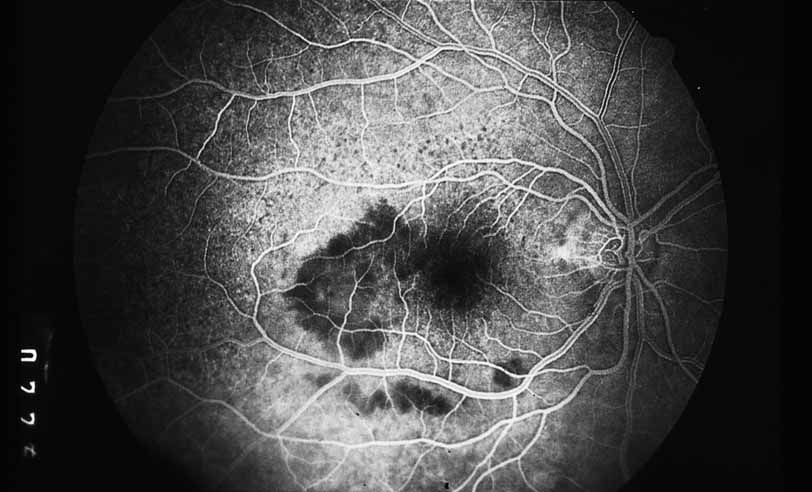

A third instance in which fluorescein angiography concentrating on the optic nerve may be helpful is in eyes with vascular engorgement of the optic nerve, especially with media opacities. Fluorescein angiography may help the clinician distinguish abnormally leaking capillaries from neovascularization. In acute multifocal hemorrhagic retinal vasculitis, optic nerve involvement is common in the early stages of the disease, 47 with optic nerve disc neovascularization seen later (see Figs. 10, 11, 12, and 13). Another fluorescein angiographic clue to the distinction between optic disc vessel engorgement and true neovascularization is the presence of associated large zones of retinal capillary nonperfusion such as those seen in sarcoidosis (see Figs. 14 and 15),34–40 acute multifocal hemorrhagic retinal vasculitis (see Figs. 10 and 11),47 or Eale disease (see Figs. 16 and 17).48–52

Fig. 13 Acute multifocal hemorrhagic retinal vasculitis. The patient underwent scatter laser photocoagulation to the zones of retinal capillary nonperfusion, which resulted in regression of the neovascularization.